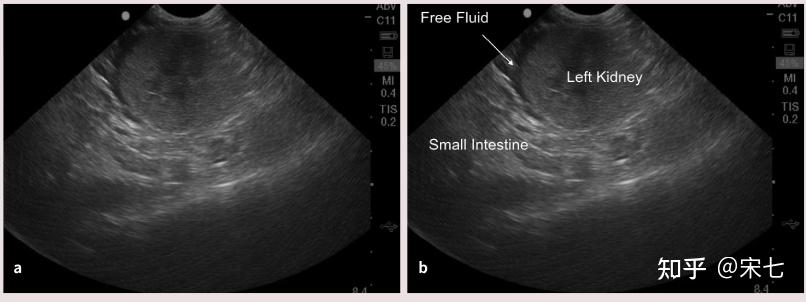

猫传腹(fip)的影像诊断

图片尺寸810x296